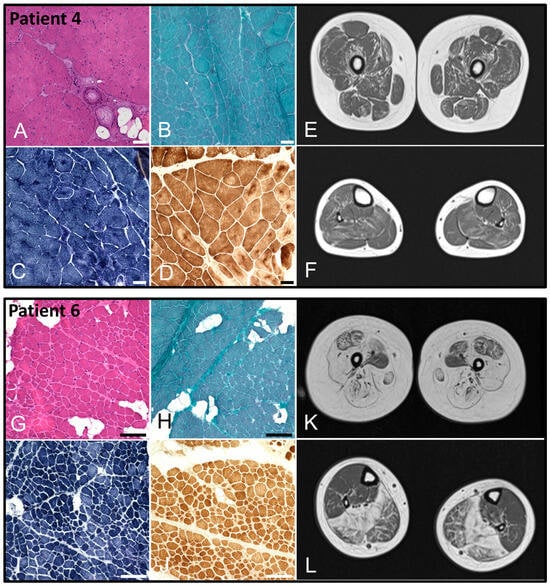

| Muscle biopsy | Fiber size variation, few internal nuclei (Figure 2) | Fiber size variation, numerous immature type 2C muscle fibers | Fiber size variation | Fiber size variation, centronuclear myopathy (Figure 3) | - | Fiber size variation, chronic active myopathy, reduced α-dystroglycan (Figure 3) | Fibrolipomatosis, internal nuclei | |